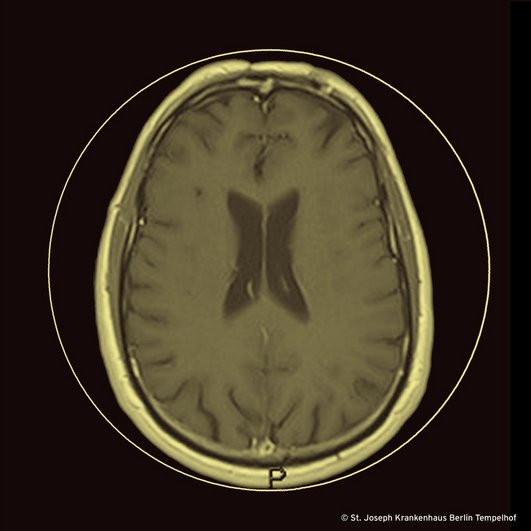

Wir haben die diagnostischen Kriterien für eine Neurotuberkulose [7] beherzigt und den Patienten mit einer antituberkulösen Therapie behandelt (ohne Steroide). In der Zwischenzeit haben wir gehofft, dass wenigstens eine der kulturellen Untersuchungen des Liquors Wachstum von M. tuberculosis zeigen würde. Diese Hoffnung erfüllte sich leider nicht. Dennoch hat sich kurz nach Beginn der Therapie der Zustand des Patienten beeindruckend gebessert. Und in den seriellen MRTs zwischen Therapiebeginn bis Mai 2024 zeigte sich, dass die lineare subependymale Kontrastmittelanreicherung des dorsalen Anteils des Pars centralis sowie des Trigonums des linken Seitenventrikels rückläufig und zuletzt nicht mehr nachweisbar war (unser Bild), und dass die Herde im ZNS weniger Signalanhebung nach KM-Gabe aufweisen. Im Liquor sahen wir eine Normalisierung aller initial ausgelenkten Parameter.